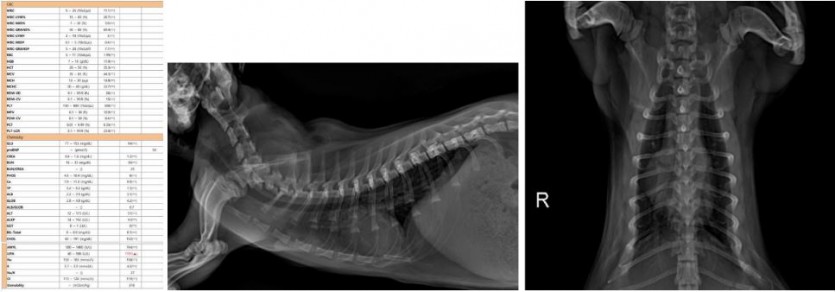

<좌 : 마취 전 혈액검사' 이상없음' 우 : 마취 전 방사선 검사 '이상없음'>

5개월령의 어린 아이로 꼼꼼한 마취 전 검사가 진행되었고, 다행히 마취 전 검사 상에 아무런 문제가 없어 수술적인 교정이 진행되었습니다. 수술 중에 경골 조면의 골절선이 확인되었고, 골절선을 잘 맞춘 뒤 핀과 와이어를 이용해 단단하게 고정해주었습니다.